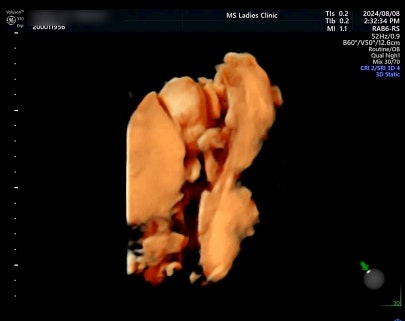

임신기록 l 23주 ~ 25주 ♥ 임산부 다래끼, 임당재검 통과

23주부터 25주 용접이 너무너무 잘 자라고 있고 포동포동해지고 있는 느낌이다 ♥ 두 검진에서는 그래도 얼...